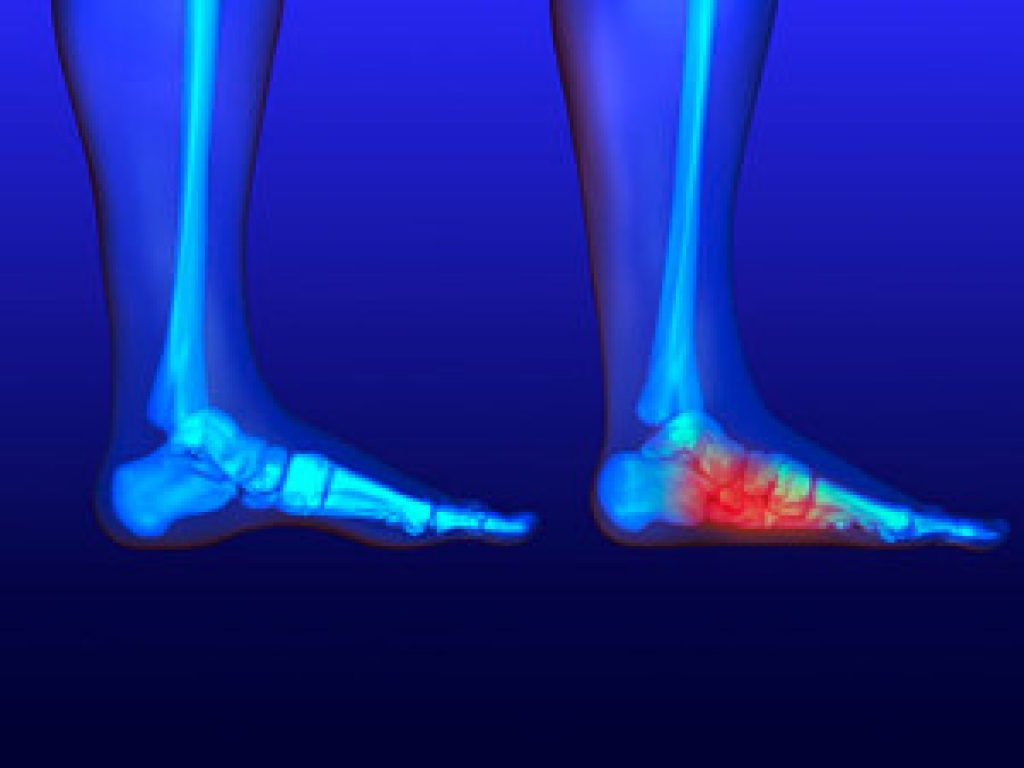

Heel fissures, or cracked heels, often occur when the skin on the feet becomes thick, dry, and less elastic. Over time, pressure from standing or walking causes the hardened layers to split, creating painful cracks that can bleed or become infected. Research into the structure of healthy and callused skin shows that excess keratin buildup reduces flexibility and traps moisture unevenly, leading to deeper fissures. Regular exfoliation and hydration help restore softness and prevent further damage. Applying urea-based or lactic acid creams softens thickened skin, while protective heel balms lock in moisture. In severe cases, debridement and professional podiatric care may be necessary to remove excess tissue and promote healing. Consistent foot care and wearing supportive shoes that reduce friction and pressure are key to keeping heels smooth, strong, and comfortable. If you are suffering with painful or chronic heel fissures, it is suggested that you see a podiatrist for expert care.

It is important to moisturize your cracked heels in order to prevent pain, bleeding, and infection. The reason cracked heels form is because the skin on the foot is too dry to support the immense pressure placed on them. When the foot expands, the dry skin on the foot begins to split.